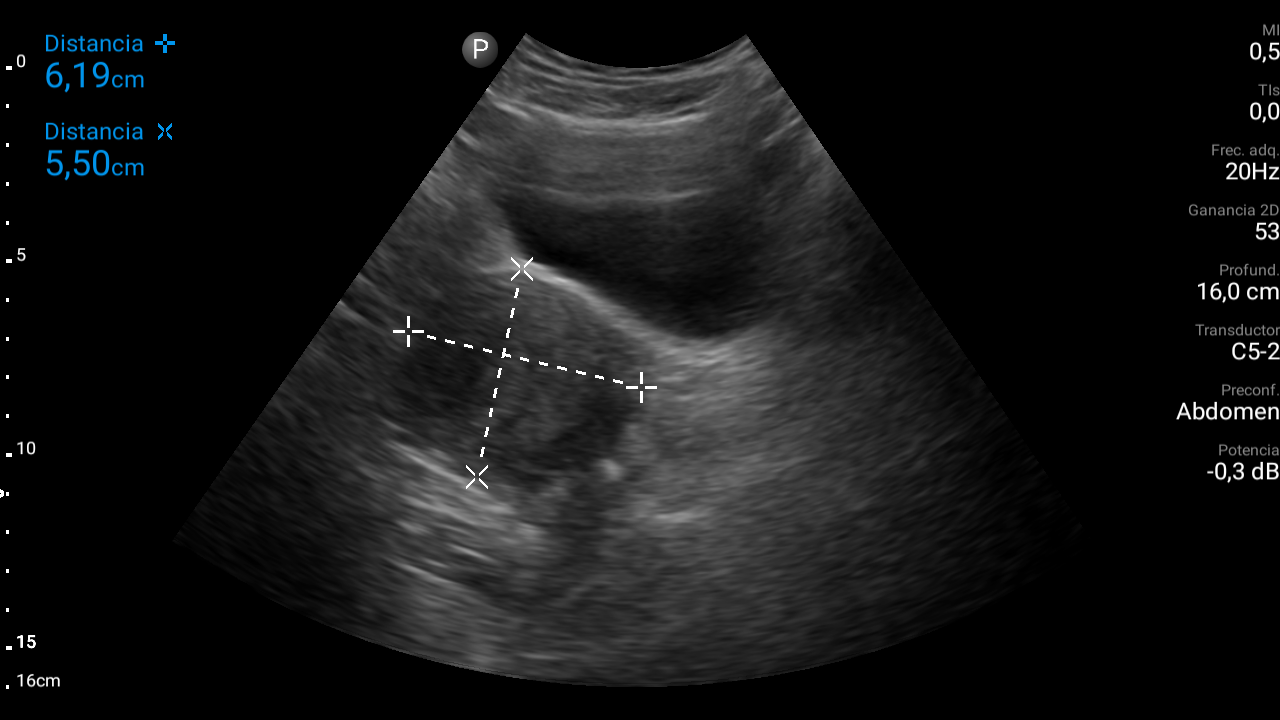

Ecografía abdominal: se observa masa hipoecoica dependiente de útero por lo que se remite de forma preferente a ginecología.

Diagnóstico: mioma uterino.El diagnóstico diferencial habría que realizarlo entre adenomitosis (ausencia de cápsula que separa la formación del tejido miometrial normal), sarcoma, leiomiosarcoma (tumor maligno), salpingitis, endometriosis, embarazo ectópico, torsión ovárica, rotura de ovario, patología urológica (cólico nefrítico…) o patología digestiva (enfermedad inflamatoria intestinal, pseudoobstrucción intestinal…).